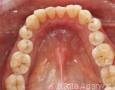

Pictures

3 Months

4 Months